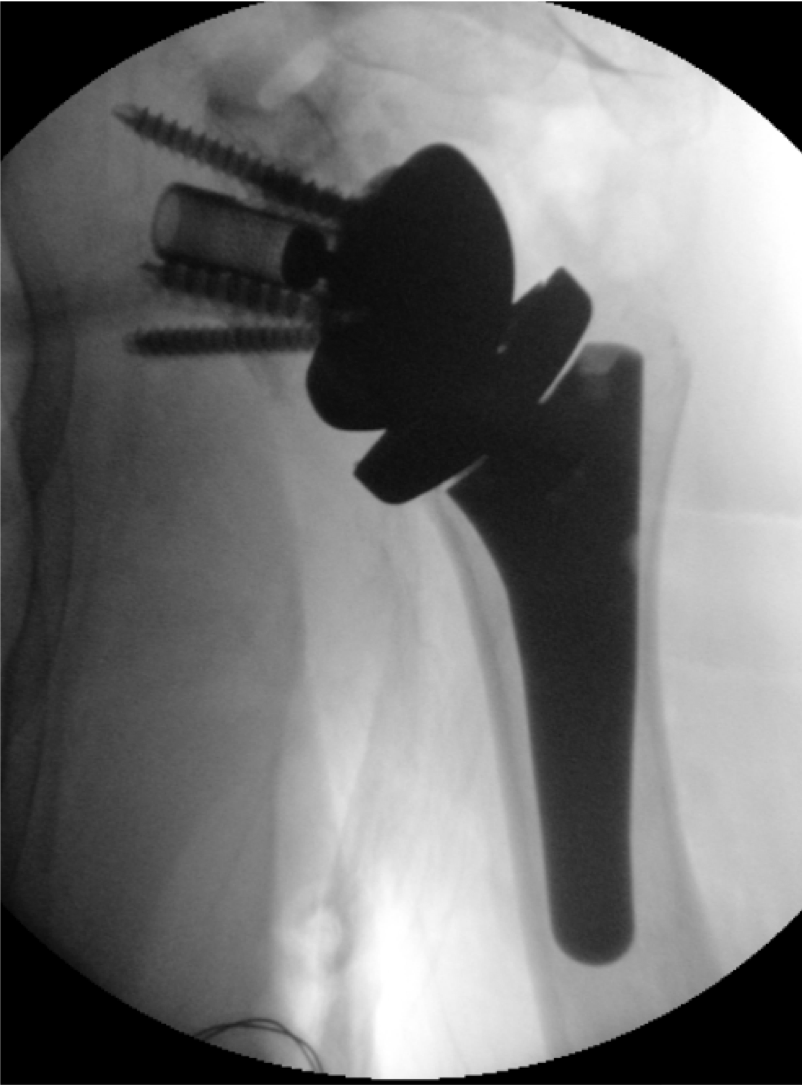

Post-op

Result

- Cementless RSA with Humeral Short Stem,

- Humeral Reverse Tray neutral

- Glenosphere ø 36 mm and PE Insert height 0

- Bio RSA carried out with 10 mm bone allograft

- Good stability and ROM

- Good inferior glenoid overhang and lateralization

- Good function and pain relieve